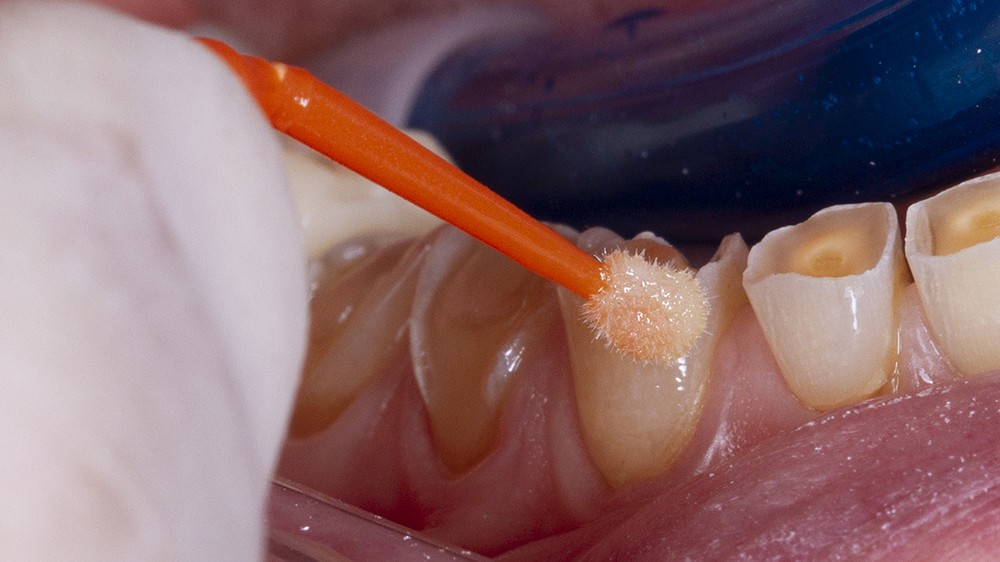

Un sablage à l’oxyde d’alumine est recommandé lorsque les usures sont marquées afin de préparer la surface de collage. Après rinçage, un mordançage à l’acide orthophosphorique est réalisé pendant 30 secondes sur l’émail et 15 secondes sur la dentine. Après un rinçage scrupuleux, un adhésif est étalé sur l’ensemble des surfaces mordancées, soufflé puis photopolymérisé (fig. 5).